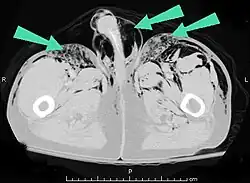

Additionally, it may result from self-injection of air during illicit drug use, particularly in individuals who inject substances intravenously or into unusual sites. There have been documented cases of subcutaneous emphysema occurring in various body regions, including the scrotum, secondary to such self-induced air injection during substance abuse.[23]

Significant cases of subcutaneous emphysema are easy to diagnose because of the characteristic signs of the condition.[1] In some cases, the signs are subtle, making diagnosis more difficult.[13] Medical imaging is used to diagnose the condition or confirm a diagnosis made using clinical signs. On a chest radiograph, subcutaneous emphysema may be seen as radiolucent striations in the pattern expected from the pectoralis major muscle group. Air in the subcutaneous tissues may interfere with radiography of the chest, potentially obscuring serious conditions such as pneumothorax.[18] It can also reduce the effectiveness of chest ultrasound.[28] On the other hand, since subcutaneous emphysema may become apparent in chest X-rays before a pneumothorax does, its presence may be used to infer that of the latter injury.[13] Subcutaneous emphysema can also be seen in CT scans, with the air pockets appearing as dark areas. CT scanning is so sensitive that it commonly makes it possible to find the exact spot from which air is entering the soft tissues.[13] In 1944, M.T. Macklin and C.C. Macklin published further insights into the pathophysiology of spontaneous Macklin's Syndrome occurring as a result of a severe asthmatic attack.